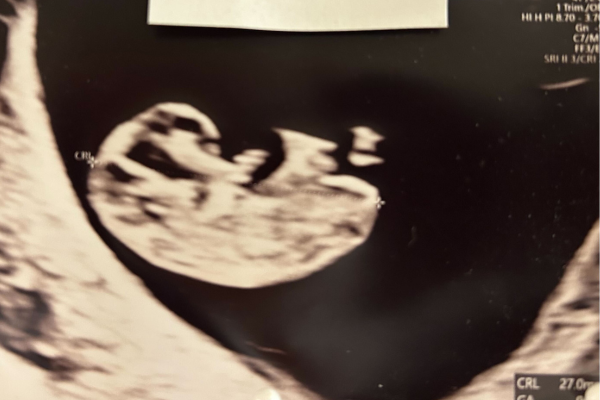

Nu er fostret blevet 18-22 mm langt og vejer cirka 2 gram. Formen ligner mere og mere et menneske. På næsen kan man se to bittesmå huller, der er på vej til at blive næsebor. Hovedet er næsten halvt så stort som kroppen, og barnet retter sig mere og mere ud. Nervesystemet, og især hjernecellerne, udvikler sig og modnes. Der dannes flest nerveceller på det sted, hvor hjernen udvikles – ca. 100.000 hjerneceller i minuttet!

Få en tidlig scanning. Det er bare helt igennem fantastisk at opleve babyen på en scanning og se hjerteblink. Det fremmer jeres tilknytning til det lille barn og gør graviditeten mere virkelig. Særligt hvis du oplever pletblødning, kan det være betryggende at se, at graviditeten udvikler sig som den skal. Læs mere her